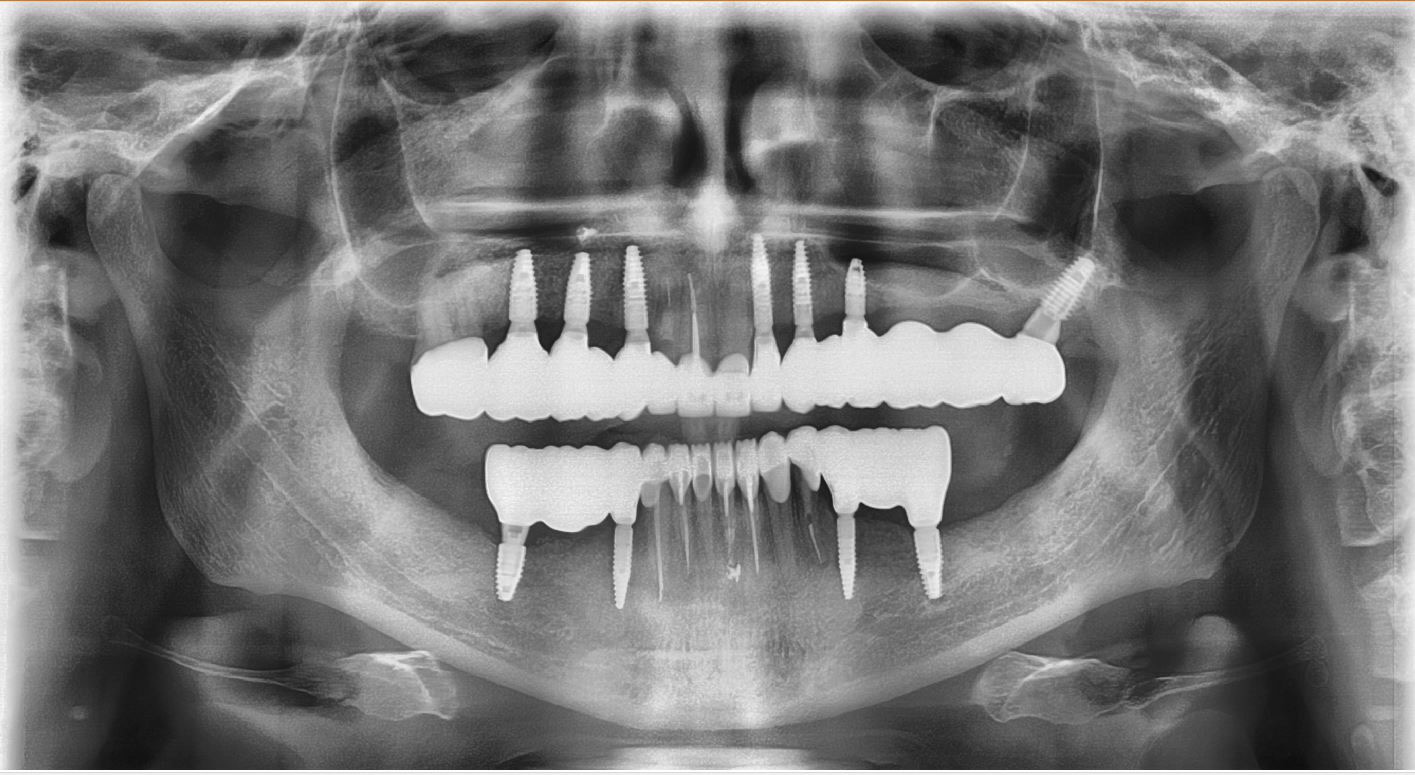

Тотальна реконструкція усмішки, відновлення функції та естетики в дуже складних початкових умовах за допомогою імплантантів та керамічних коронок. Дізнатися вартість >>>